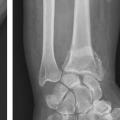

L’extrémité inférieure du radius est biarticulaire, en répondant à la fois au carpe par la glène radiale et à la tête de l’ulna par l’incisure ulnaire du radius, expliquant qu’entre 50 et 80 % des fractures de l’extrémité inférieure du radius ont une participation articulaire.8 Elle constitue un bloc épiphysométaphysaire distal hétérogène et complexe de forme schématiquement triangulaire à base médiale et à sommet latéral qui s’effile par la styloïde radiale (fig. 1).

Les corticales ventrale et médiale sont épaisses et résistantes, à la différence des corticales dorsale et latérale, plus fines (fig. 2), expliquant en partie la fréquence des déplacements fracturaires en bascule postérieure et latérale de l’épiphyse radiale avec horizontalisation de la ligne bistyloïdienne.6 L’extrémité inférieure du radius est par ailleurs remplie d’un tissu osseux spongieux dense et renforcé de travées verticales s’opposant aux contraintes axiales transmises du carpe au squelette antébrachial. L’ostéoporose a une action péjorative globale sur cette structure, en altérant à fois la densité du tissu spongieux, avec raréfaction des travées osseuses, mais aussi l’épaisseur corticale.

La surface articulaire distale, encroûtée de cartilage, répond au carpe distalement et présente deux facettes, scaphoïdienne et lunarienne (fig. 3), séparées par une crête de direction antéropostérieure. Cette surface articulaire a une double concavité transversale et sagittale. Il est crucial de retenir qu’elle possède une double inclinaison ventrale (10 à 12° en moyenne dans le plan sagittal) et médiale (22 à 24° en moyenne dans le plan coronal), très spécifique, qu’il faudra s’efforcer de restituer et de maintenir dans le traitement de la composante métaphysaire de ces fractures (fig. 4). L’index radio-ulnaire distal, défini par la longueur relative du radius par rapport à l’ulna, est le troisième critère morphologique à évaluer (fig. 4). Ce dernier, dont les valeurs normales sont très variables, est en moyenne neutre à 0 mm (-3 mm à +2 mm).